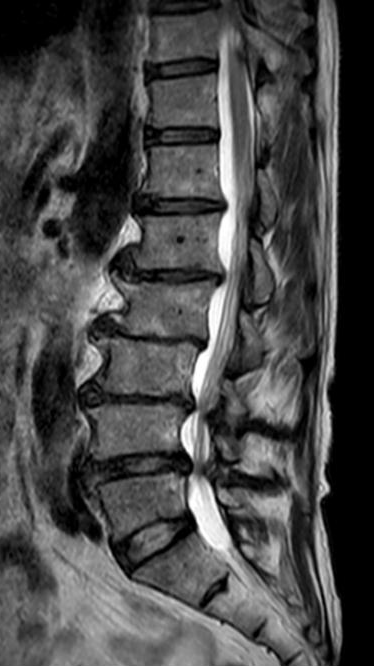

陈勇主任团队顺利为患者置入椎弓根螺钉。术后患者腰腿痛症状较术前明显缓解,肢体活动无障碍,术后3天即在脊柱支具外固定的辅助下下地行走,术后第7天患者恢复情况良好,顺利出院。

▲术后复查X线、CT